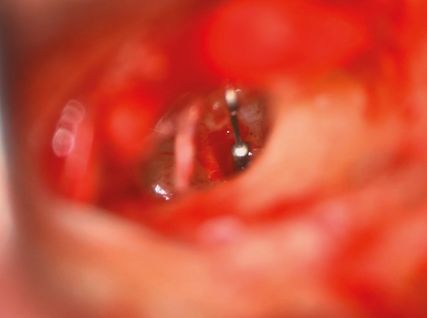

Die Therapie der Wahl stellt die operative Sanierung durch die Stapesplastik dar. Dabei wird der versteifte Stapes durch eine Protheseersetzt, die durch die perforierte oder teilentfernte Stapesfußplatte ins Innenohr ragt und am Incus fixiert wird. Im Laufe der Zeit haben sich Variationen der Operationstechnik ergeben und verschiedene Prothesenformen wurdenentwickelt. Die Wahl des Vorgehens und der Prothese hängt maßgeblich von den Vorlieben und der Praxis des Operateurs ab.10

In den Abbildungen 2–4 sind die Operationsschritte, wie sie in der Regel in unserer Klinik erfolgen, dargestellt.